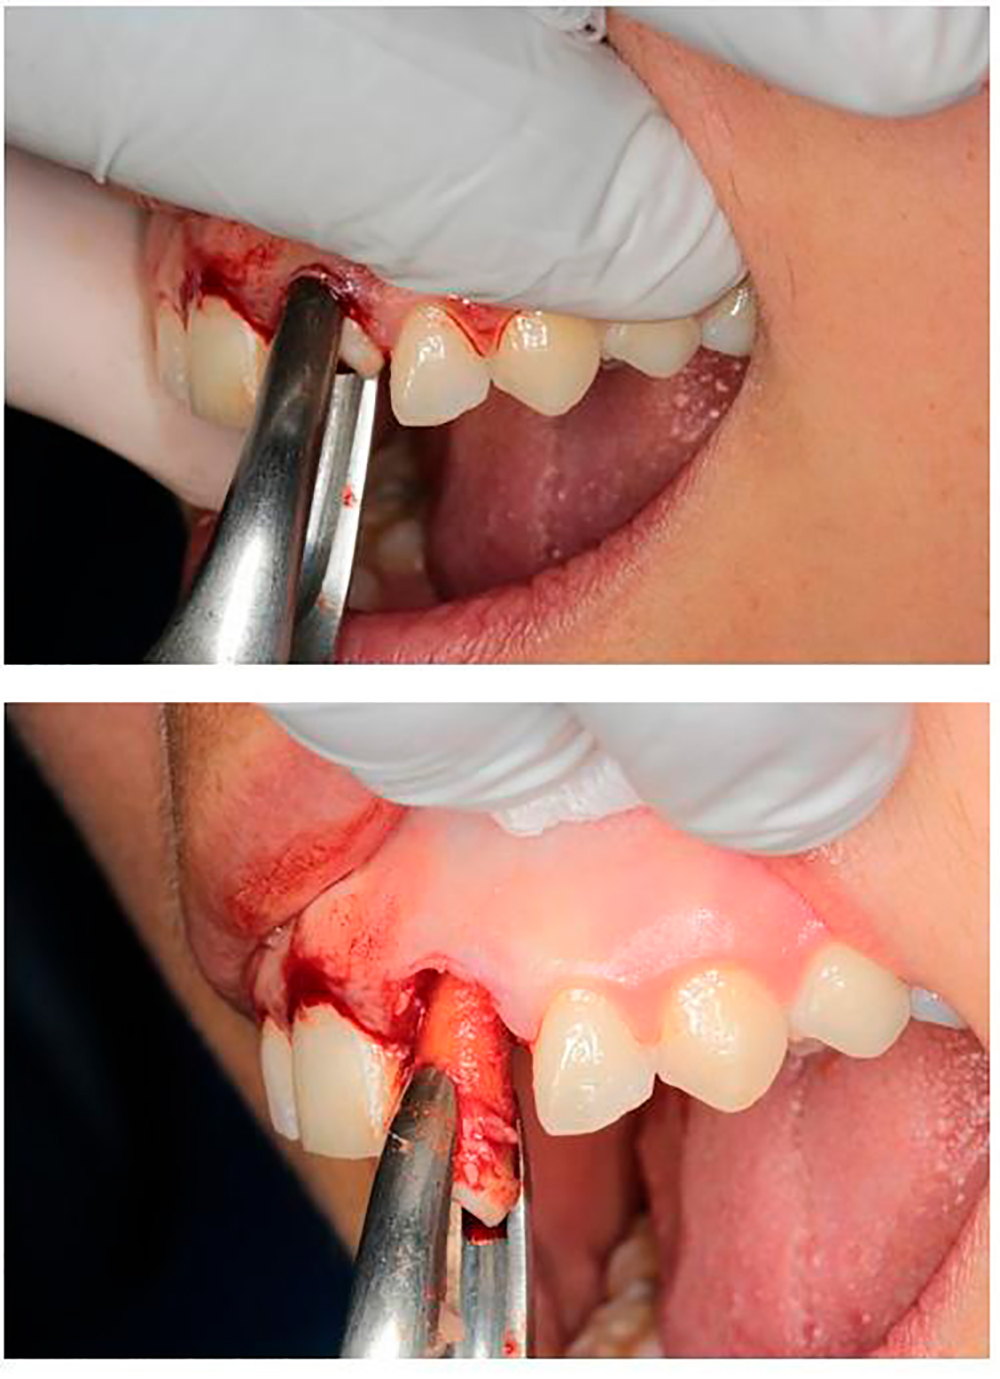

Initial situation Prior extraction

Extraction of the damaged restoration